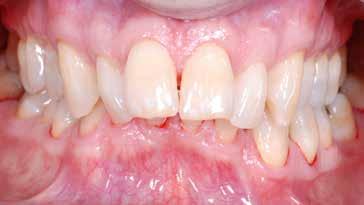

Presentazione del caso > F.V, bambino di cinque anni, presenta una malocclusione di II Classe scheletrica, III Classe dentale molare e canina destra e sinistra, morso inverso anteriore. Le arcate dentali mostrano usura degli elementi dentari anteriori a causa dell’occlusione patologica. Le linee mediane, superiore ed inferiore, sono centrate; il frenulo labiale superiore patologico per un’eccessiva estensione inter-incisale.

Dall’esame clinico si evince la III Classe dentale, l’inversione anteriore e l’over-jet negativo.

Una volta ottenuta la correzione del rapporto molare ed incisale, l’apparecchio elastodontico verrà portato dal paziente solo durante la notte per stabilizzare il risultato ottenuto e guidare l’eruzione degli elementi dentari per un totale di quattordici mesi di terapia. ad inizio trattamento :

Considerazioni > L’analisi cefalometrica ad inizio trattamento dimostra la II Classe scheletrica con protrusione del mascellare superiore e prognazia mandibolare; tendenza alla crescita verticale. L’esame clinico evidenzia una protrusione mandibolare funzionale.